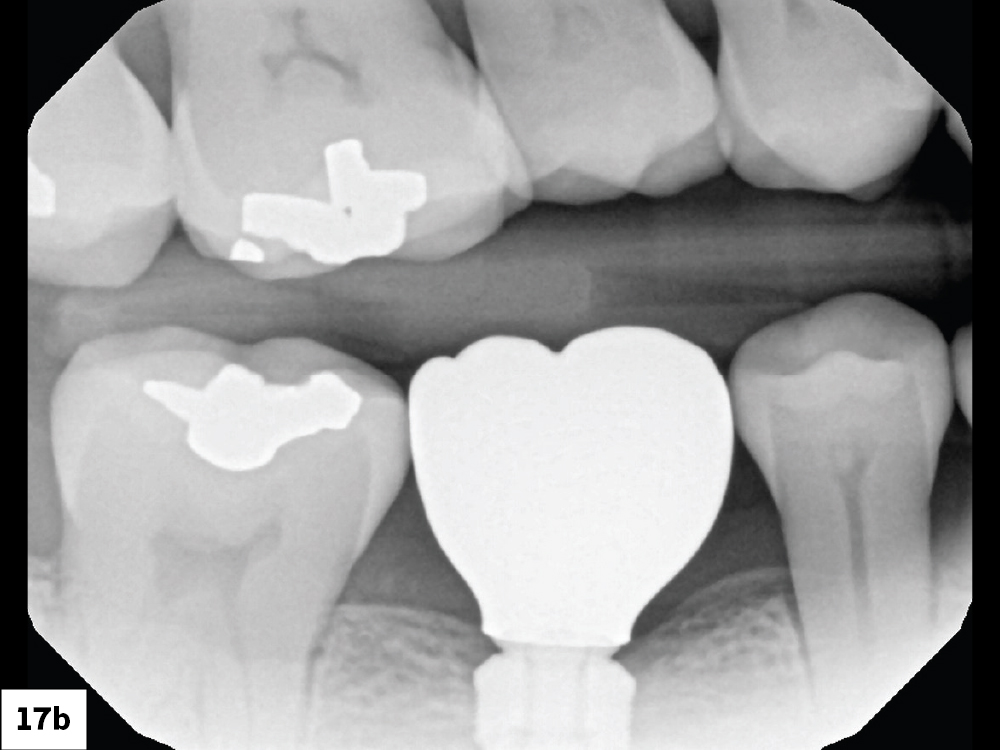

Final BruxZir Esthetic Screw-Retained Crown

Access Channel Filled with Teflon Tape

Figures 17a, 17b: The final BruxZir Esthetic screw-retained crown was fabricated by Glidewell. After it was seated, the access channel was filled with Teflon tape and sealed with composite.